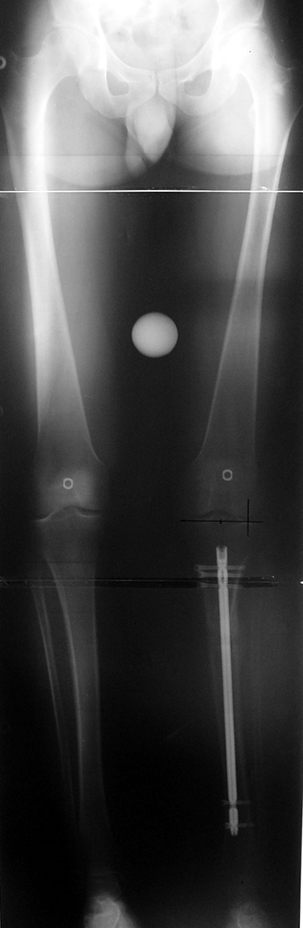

3. POSTTRAUMATIC LOWER LIMB SHORTNESS (MALUNION)

This type of shortness occurs after a fracture heals in a shortened position. Most cases are seen in adults and can be treated with one lengthening operation. Additional deformities can be corrected simultaneously. Most of these cases can be treated with lengthening over nail or just corrections and intramedullary nailing.